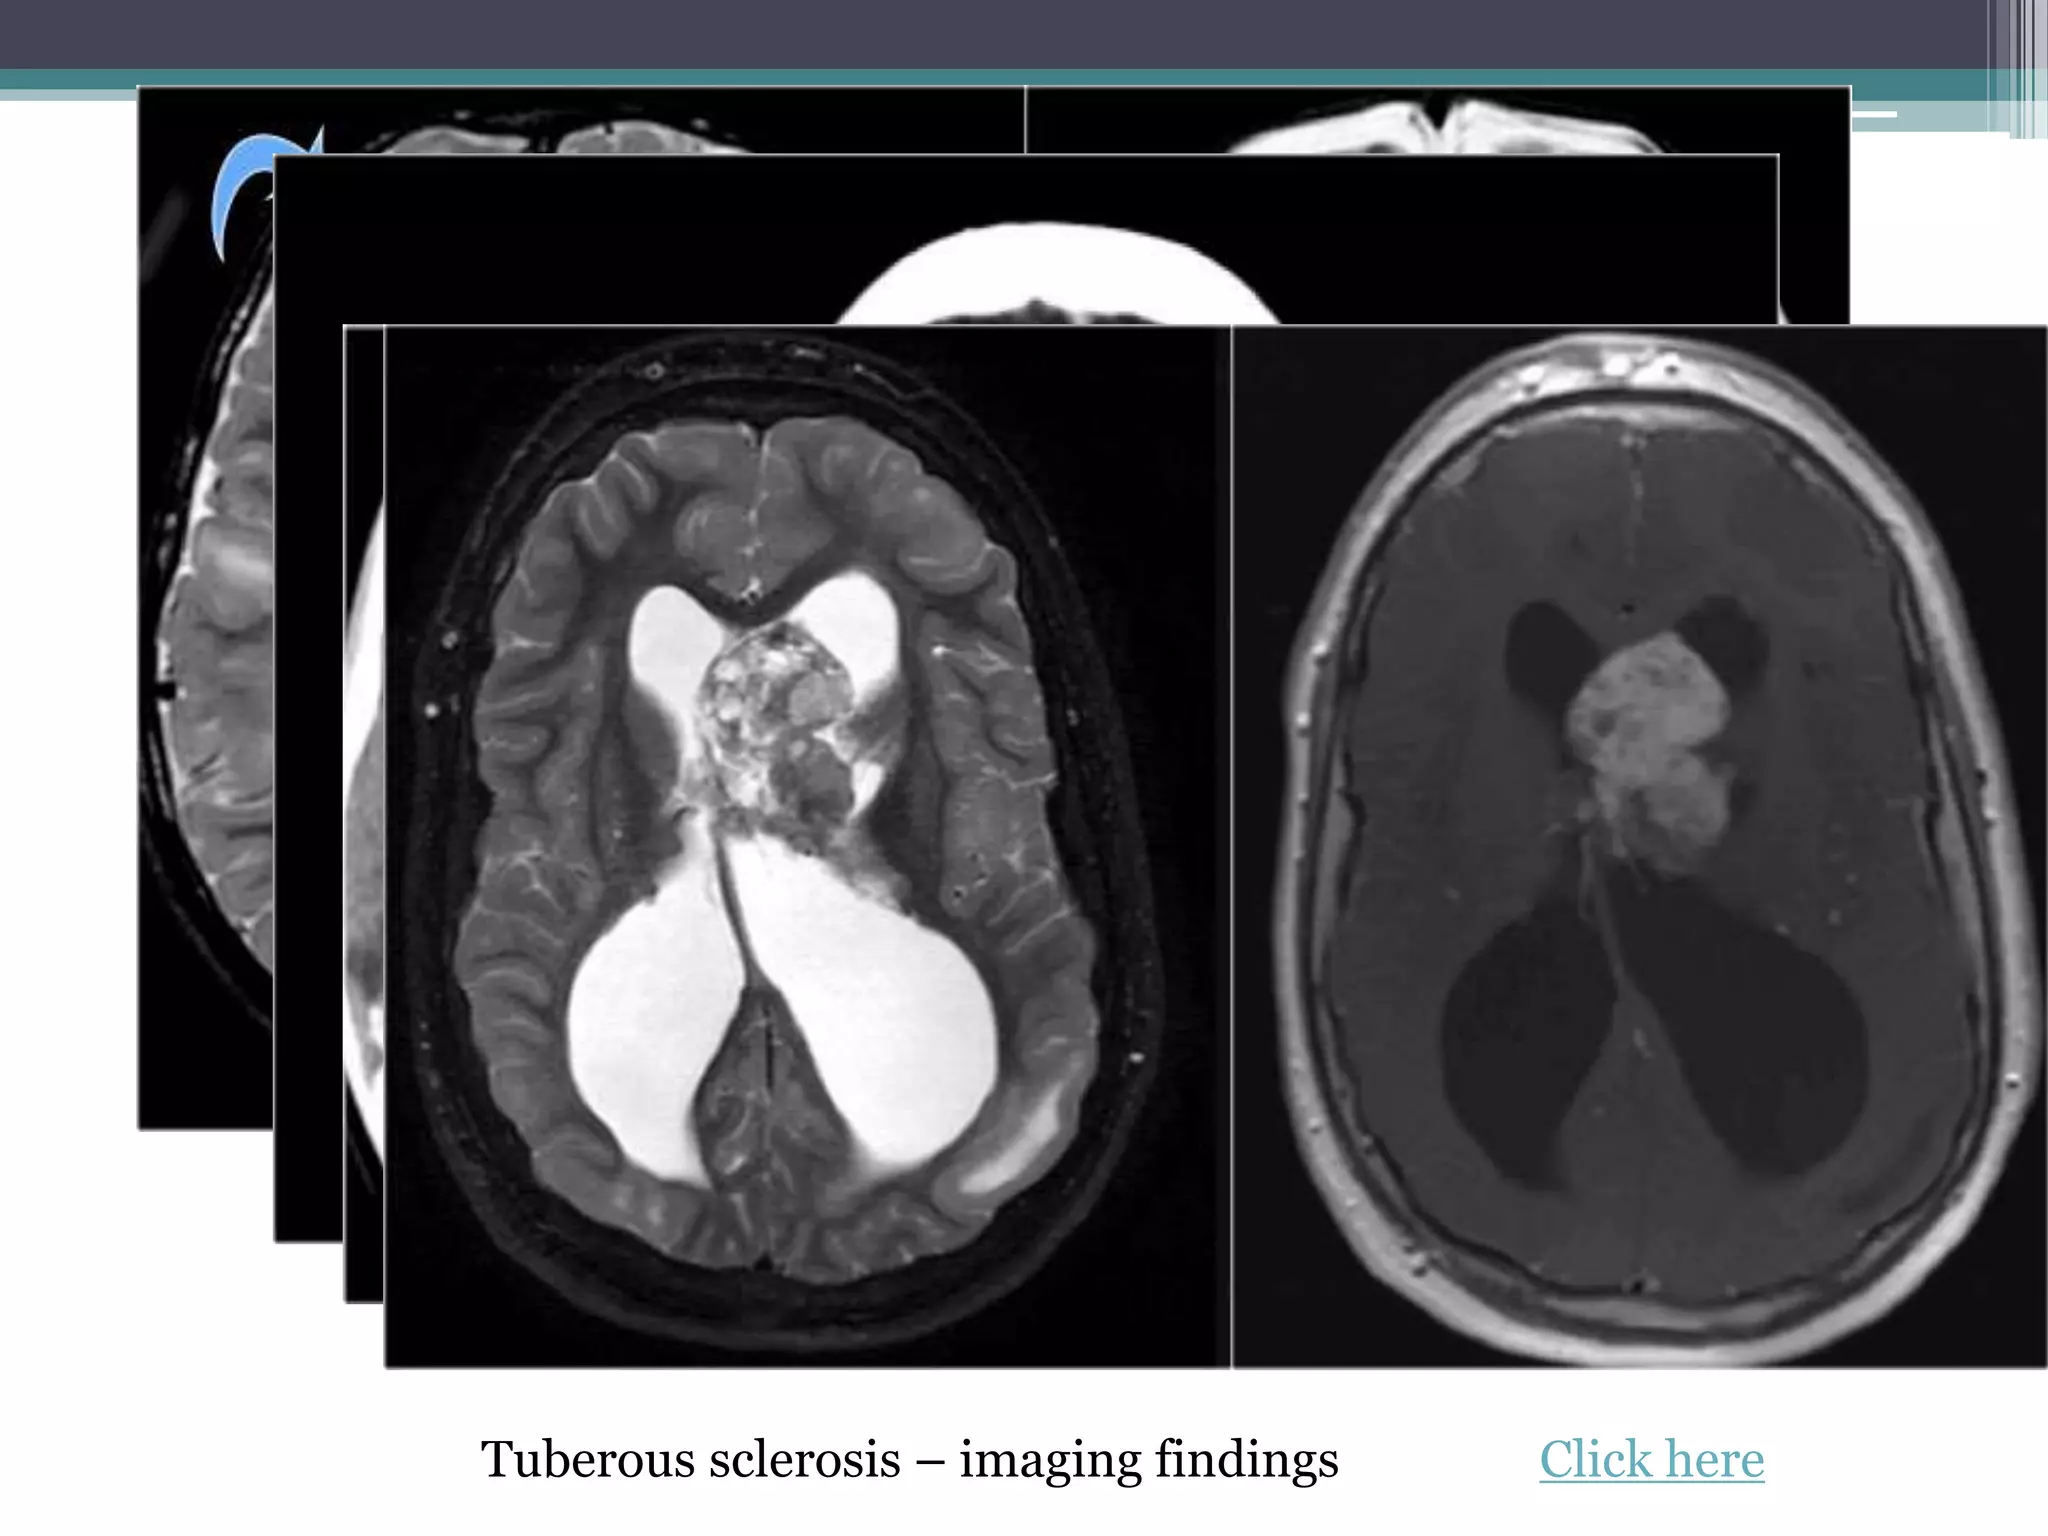

8. Tuberous Sclerosis • hamartomas in many organs

including angiomyolipoma of the

kidney, cardiac rhabdomyoma and

cortical and subependymal tubers in

the brain.

• Cortical hamartomas, subependymal

tubers, SEGA, white matter

abnormalities. Click here

Tuberous sclerosis – imaging findings Click here

Tuberous sclerosis –imaging findings Click here